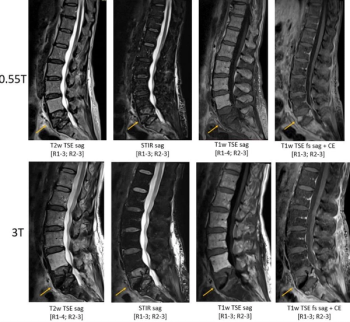

In a study of patients who had lumbar spine MRI exams at 0.55T, 1.5T and 3T, researchers found that 0.55T MRI provided acceptable diagnostic quality across all sequences for varying pathologies including degenerative joint disease, compression fractures and osseous metastatic disease.